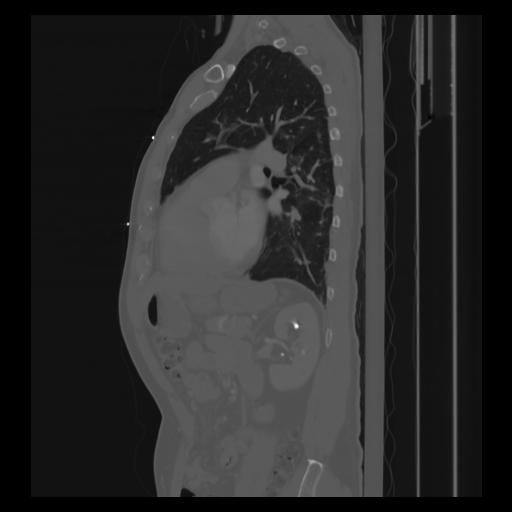

30 CUERPO,CE,Sagittal,3.000,CUERPO,Sagittal,